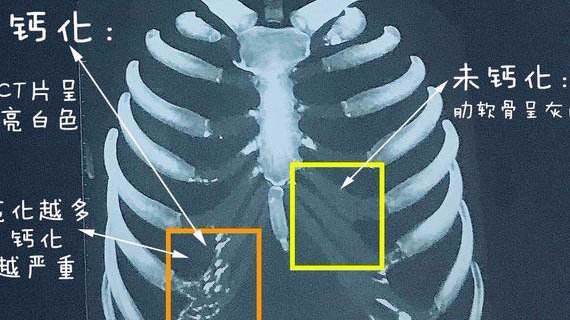

这个肋骨是不是钙化严重不能做肋骨鼻啦

图片尺寸1078x1502

肋软骨钙化是什么钙化了是不是就不能做肋软骨隆鼻

图片尺寸570x320